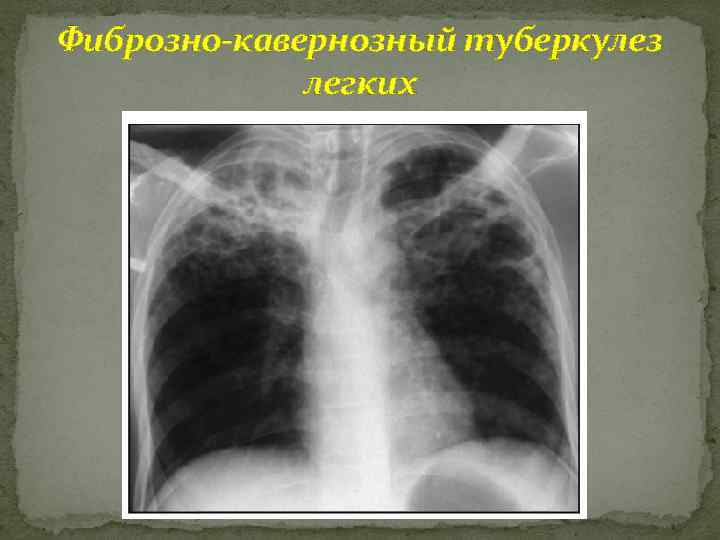

Фиброзно-кавернозный туберкулез легких Рентгенография линейная томография КТ: одиночные или множественные полости деструкции различных размеров с неровными наружными контурами; преимущественная локализация каверн - верхушки и задние сегменты верхних долей; пораженные отделы легких уменьшены в объеме и неравномерно уплотнены; очаговые тени отсева как в окружности полостей, так и в отдалении

Фиброзно-кавернозный туберкулез легких